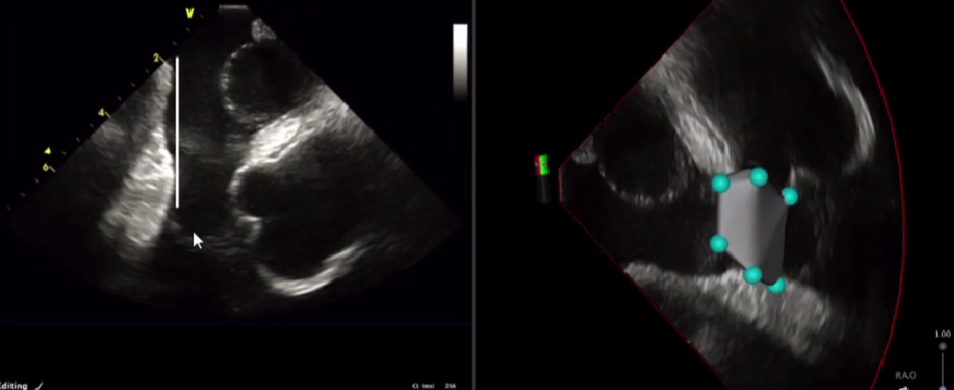

ICE-相对平坦的三尖瓣峡部

连接凹陷两端的肌束

超声观察到右冠状动脉

比较长的三尖瓣峡部